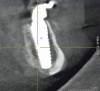

When such instances occur, whether in the mandible or maxilla, the author first attempts to place a larger-diameter implant of the same length as the implant that failed to achieve high initial torque value. Should this adjustment prove ineffective, a longer implant of a larger diameter is then used. In the maxilla, the longer implant may engage the vomer or lateral piriform rims to achieve apical stability.13 In the mandible, the author achieves primary implant stability by engaging the cortical bone at the inferior border of the mandible with the apical portion of the dental implant (Figure 14 and Figure 15).